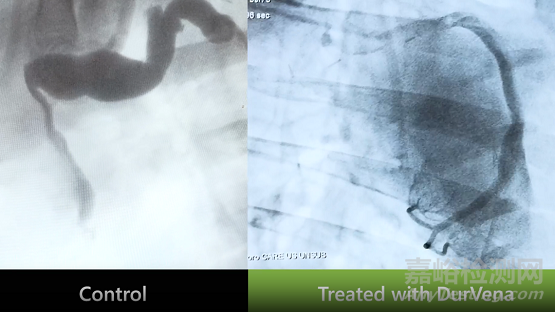

通過動(dòng)物試驗(yàn)可以明顯看到,沒有使用PTP的橋血管變得迂曲、擴(kuò)張,導(dǎo)致血液流動(dòng)不暢,而PTP技術(shù)處理的橋血管擴(kuò)張非常小,能夠保持血管暢通。